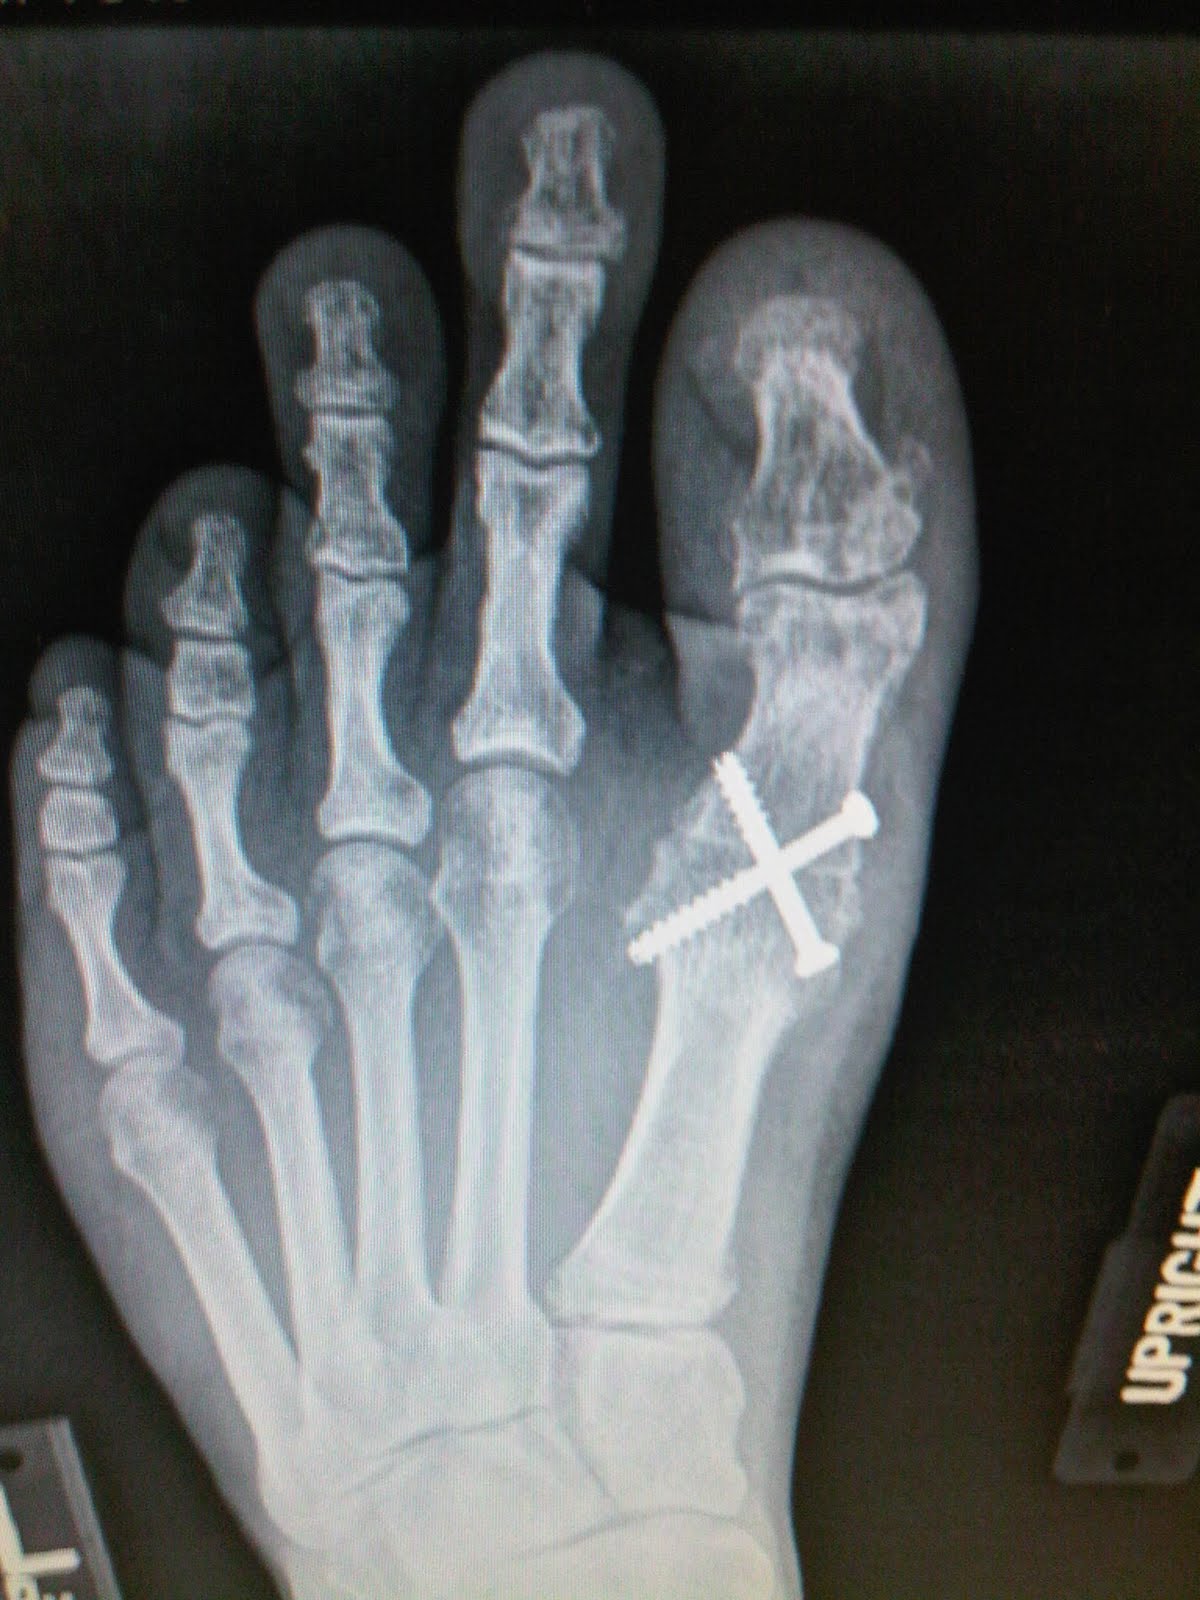

Running With Toe Fusion . Hallux limitus means the ‘stiff big toe’. A big toe fusion is performed as a definitive procedure to treat painful hallux rigidus (big toe arthritis) or sometimes for severe bunions. Just a update to say i have been running over 4 mile 3 times a week with no problems. Removal of joint surfaces preserves the joint while. Find out how in this article. Big toe fusion surgery is often recommended for patients suffering from big toearthritis and severe bunions. Though small, it can become a major factor that can hamper your running performance. The invasive procedure is extremely helpful in correcting toe malformation and reducing pain in the metatarsophalangeal joint. The two usual procedures are joint fusion and removal of joint surfaces. Hit 6 months since op tomorrow and. Big toe arthritis (also known as hallux rigidus) can cause pain and swelling and lead to difficulty. A first mtp joint fusion is a surgical procedure to treat arthritis of the big toe.

The two usual procedures are joint fusion and removal of joint surfaces. A big toe fusion is performed as a definitive procedure to treat painful hallux rigidus (big toe arthritis) or sometimes for severe bunions. Removal of joint surfaces preserves the joint while. A first mtp joint fusion is a surgical procedure to treat arthritis of the big toe. Hit 6 months since op tomorrow and. Big toe fusion surgery is often recommended for patients suffering from big toearthritis and severe bunions. Just a update to say i have been running over 4 mile 3 times a week with no problems. Though small, it can become a major factor that can hamper your running performance. Big toe arthritis (also known as hallux rigidus) can cause pain and swelling and lead to difficulty. Find out how in this article.

TOE FUSION SURGERY London Foot and Ankle